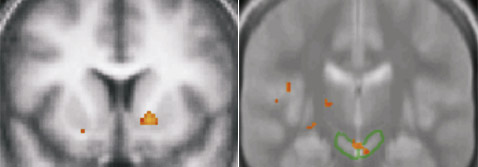

Учёным удалось установить, что у большинства подопытных при выборе в пользу незнакомых объектов активизировались полосатое тело (Corpus striatum) и чёрная субстанция (Substantia nigra) головного мозга.

Нейрофизиологи считают: эти отделы являются ключевыми в мозговой системе вознаграждения, которая стимулирует человека положительными эмоциями и ощущениями.

Слева – активизация полосатого тела, а справа – области чёрной субстанции. Для обеспечения статистической значимости результатов каждый подопытный участвовал в 20 раундах испытаний (иллюстрация Bianca Wittmann, Nathaniel Daw et al./MEMBRANA). |